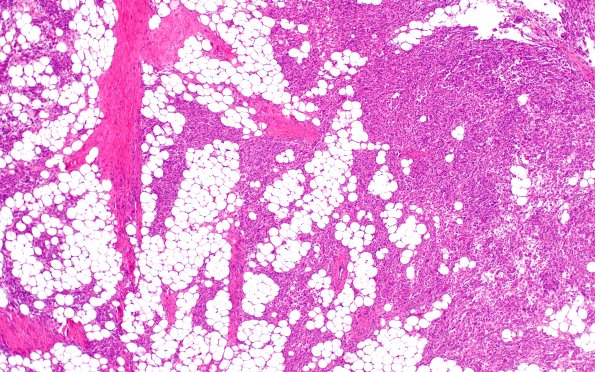

17C1 Meningioma, lipidized (Case 17) 4X

17C1-4 There is extensive lipidization of tumor cells as well as presence of secretory material. (H&E)